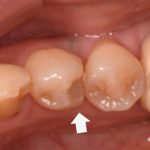

歯が欠けて物が詰まりやすい ダイレクトボンディングによる虫歯治療

治療前 治療後 性別 女性 相談内容 歯が欠けた カウンセリング・診断結果 プラ ...